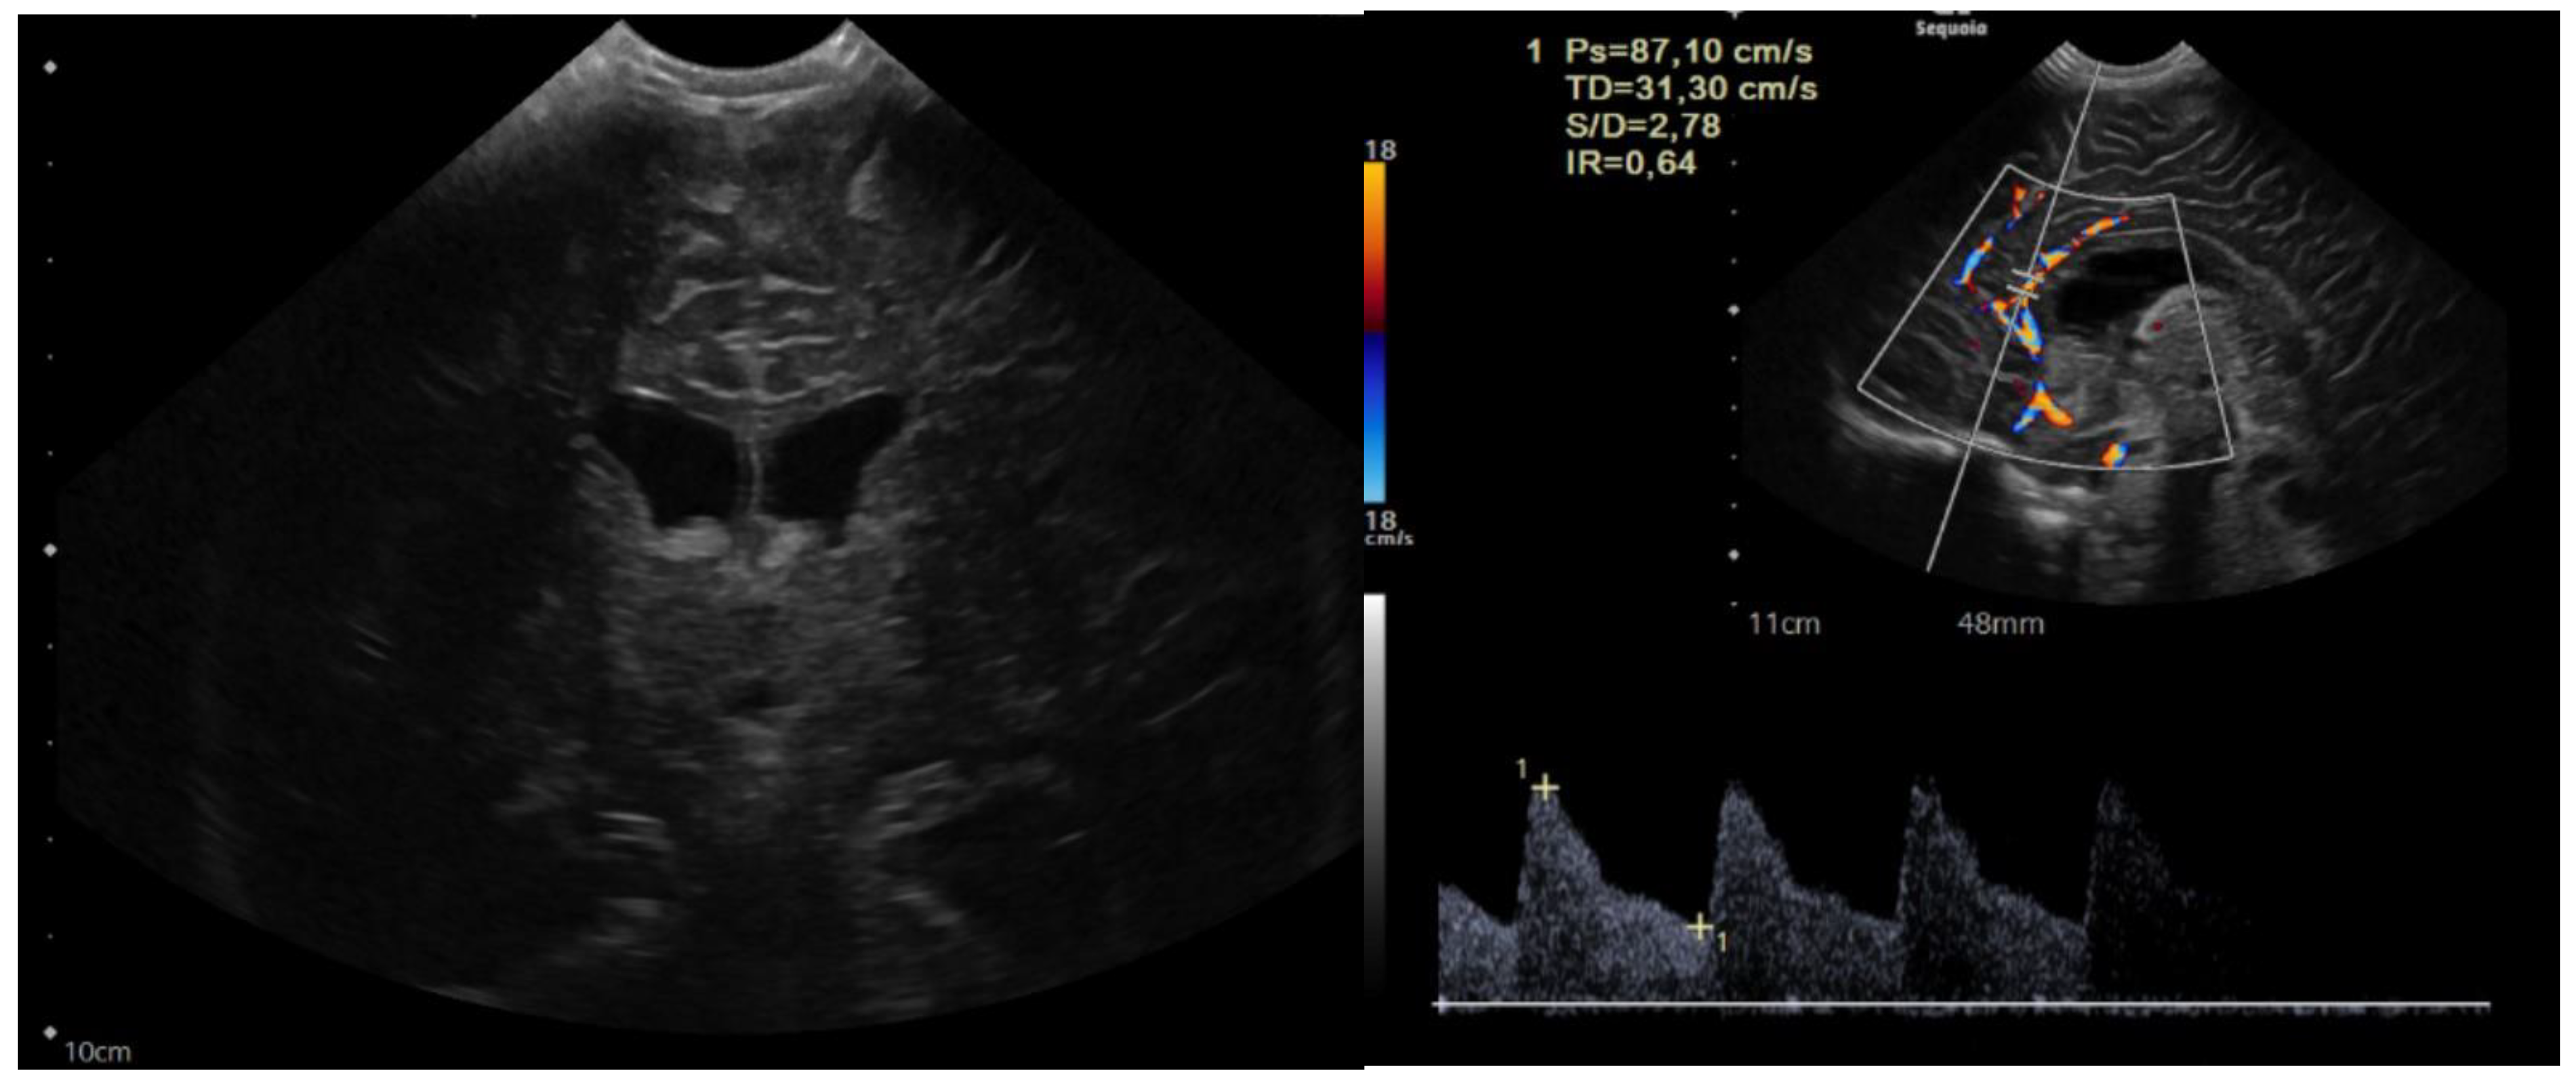

The child was 9 months old with eutocic delivery at 40 gestation weeks, and, according to the parents started to develop ataxia and hypotonia at 6 months old. She developed repeated morning and orthostatic vomiting. The head circumference was at the 98th percentile (46.5 cm), and a cerebral ultrasound (US) showed enlarged lateral ventricles (Figure 1).

Figure 1.

Sagittal and coronal US showing dilated lateral ventricles. Echocolordoppler showed augmented resistance and pulsatility indexes, speaking in favor of augmented intracranial pression.